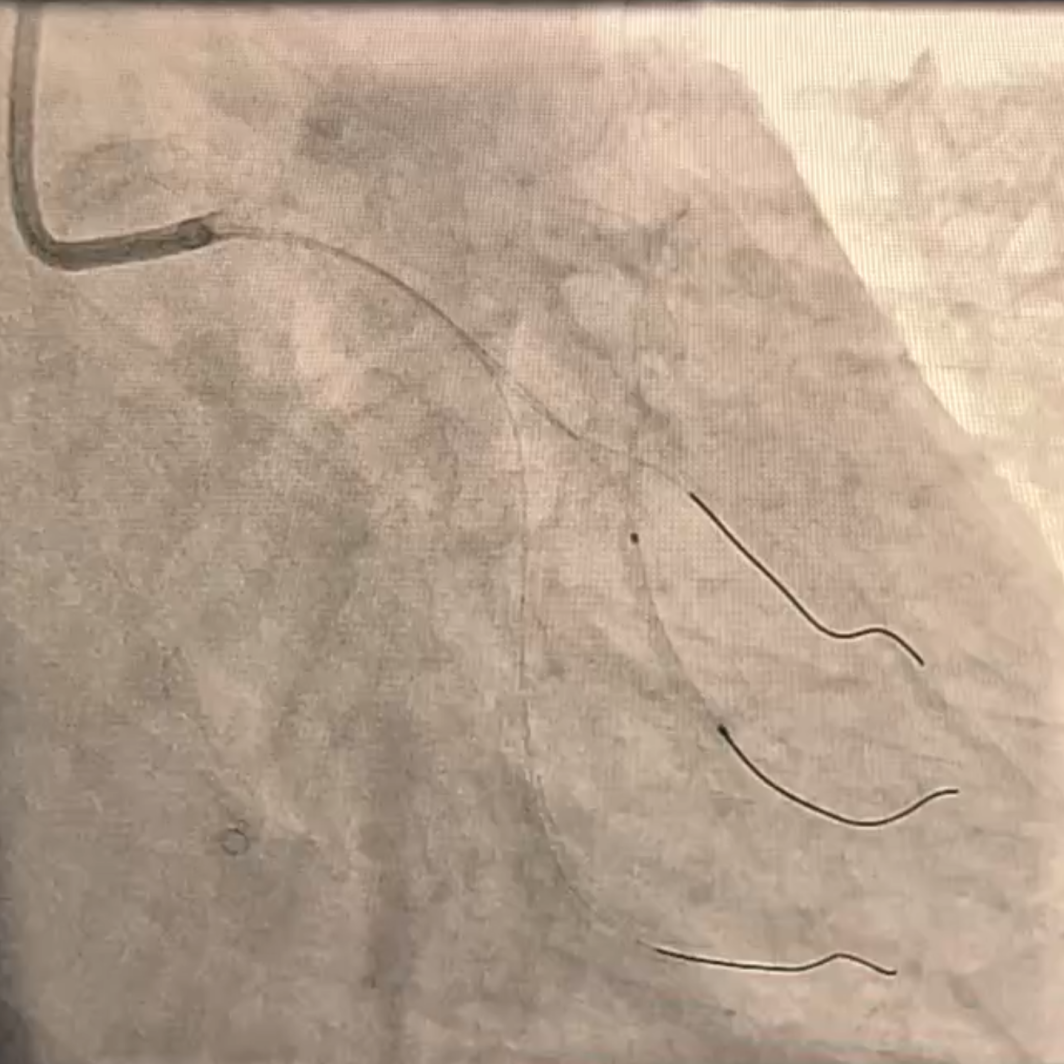

IVUS检查:提示LAD近中段钙化病变伴360°环形钙化,狭窄最重处90%。2.0-2.5球囊逐级扩张后,支架无法通过。

冲击波治疗:使用2.5×12mm、3.0×12mm 国产冲击波球囊进多次预处理LAD近中段病变。